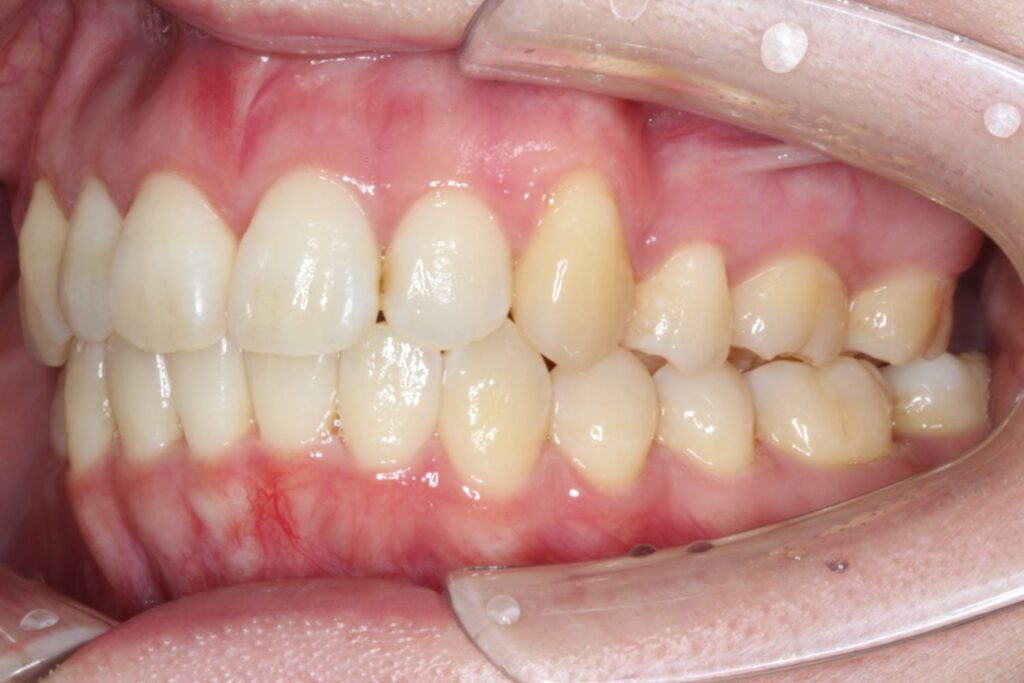

After

治療後は上顎の前歯が引っ込み、歯のがたつきも改善しています。

そうすることで、見た目だけではなく、前歯でものが噛み切りやすい機能的な歯並びが達成されました。

上顎の歯のみを抜歯していますが、噛み合わせのバランスには全く問題ありません。